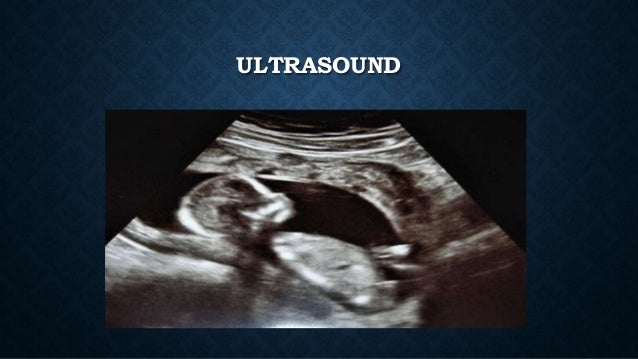

Praktikumsplätze dresden modedesign: hier findest du aktuelle praktikumsplätze in dresden für den bereich modedesign. praktikumsstellen breech presentation mode of delivery für schüler . Validation: this guideline was compared with the 2006 american. college of obstetrician's committee opinion on the mode of term singleton breech delivery and . Overview. breech presentation is defined as a fetus in a longitudinal lie with the buttocks or feet closest to the cervix. this occurs in 3-4% of all deliveries. the percentage of breech deliveries decreases with advancing gestational age from 22-25% of births prior to 28 weeks' gestation to 7-15% of births at 32 weeks' gestation to 3-4% of.

Jun 15, 2016 breech presentation mode of delivery breech presentation is defined as a fetus in a longitudinal lie with the buttocks or feet closest to the cervix. this occurs in 3-4% of all . Section has become the normal mode of breech delivery. however, breech presentation, whatever the mode of delivery, is associated with increased risk of subsequent handicap. 4 this suggests that failure to adopt the cephalic presentation may in some cases be a marker for fetal impairment. 3. identification and assessment of evidence.